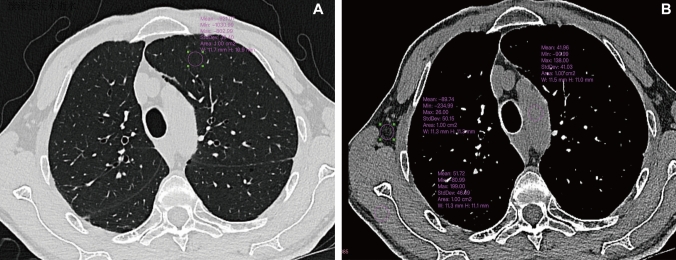

Purpose: To characterize invasion-associated CT features in pulmonary subsolid nodules using low-dose ultrahigh-resolution (UHR) photon-counting CT (PCCT) images and evaluate UHR's diagnostic superiority over standard high-resolution (HR) images.

Methods: Patients with subsolid lung adenocarcinoma were recruited for chest scan on PCCT to obtain UHR and standard HR images between November 2023 and May 2024. Nodule characteristics were visually assessed and histogram features were extracted from each nodule. Image quality and radiation dose at previous energy-integrating detector CT (EID-CT) of 30 patients were compared with those of PCCT. Differences between UHR and standard HR, PCCT and EID-CT were compared using paired McNemar-test or paired Wilcox-test.

Results: One hundred and eighty-four patients with 203 subsolid nodules were collected including 77 precursors, 77 minimally invasive adenocarcinoma (MIA) and 49 IA. UHR significantly outperformed standard HR in revealing CT findings including larger nodular diameter and solid-component diameter, more frequency of heterogeneous attenuation, lobulation, bubble-like sign, air bronchogram, pleural indentation and vascular sign (all P < 0.05). Additionally, UHR images exhibited significantly greater value in histogram-derived parameters compared to standard HR images (all P < 0.05), except for "Median," "Minimum." Furthermore, the radiation dose in PCCT was half of that in EID-CT (effective dose: 1.32 ± 0.27 vs. 3.85 ± 1.65/mSv, P < 0.001. CDTIvol: 2.97 ± 0.53 vs. 6.90 ± 2.97/mGy, P < 0.001), with image quality significantly better in PCCT.

Conclusion: The UHR protocol on PCCT provides a magnified perspective to reveal CT characteristics of invasive growth in subsolid LUAD, previously undetectable on standard HR images, achieving halved radiation dose and better image quality than EID-CT.